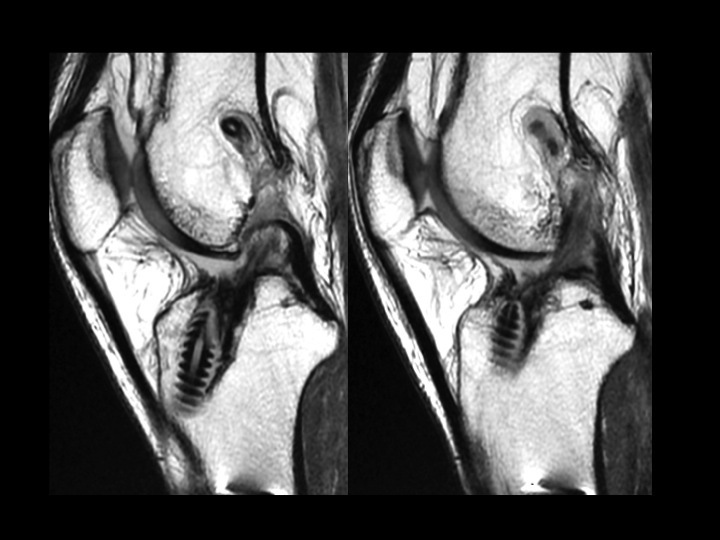

Figure 2 for case ACL graft device ( RID5523 )

Figure 2

There is fragmentation of one of the 2 bioabsorbable interference screws in the tibial tunnel, with a fragment situation in a cyst superficial to the tibial tunnel. The ACL graft is markedly attenuated. The last slide shows the failed, fragmented bioabsorbable femoral crosspin (arrow) from the initial reconstruction in 2011. Might be time for a Bone-Patellar Tendon-Bone autograft with metallic fixation?